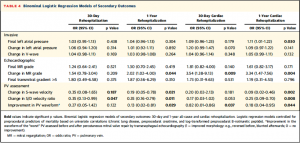

Table 4では慢性肺疾患、BNP値、クレアチニン値を用いたbinominal logistic regression modelにより、二次エンドポイント (30日/1年時での再入院、心原性の要因での再入院)について関連因子を解析した。有意な結果を全部記載すると大変なので、表を参照。PV波形の改善は1年時の再入院、30日/1年時での心原性再入院に関連していた。

(Table 4)

(Table 4)